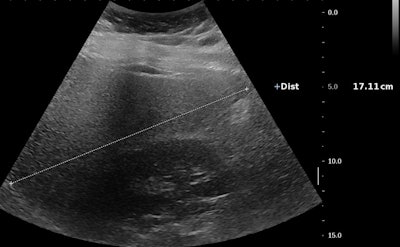

Échographie d'une jeune fille de 14 ans souffrant d'obésité sévère (indice de masse corporelle [IMC], 42 kg / m2). Il existe une hépatomégalie associée à une augmentation de l'échogénicité hépatique par rapport au rein droit et à une atténuation correspondant à une stéatose sévère. Ci-dessous, le même patient présente une augmentation du ratio foie / reins. Toutes les images avec l'aimable autorisation de Pr Stéphanie Franchi-Abella, PhD.La détection précoce est importante, car le régime alimentaire peut inverser le processus au début de la maladie. Cependant, la détection et la quantification de la teneur en graisse du foie et de la fibrose et de l'inflammation associées, indispensables au diagnostic de la NASH, restent difficiles chez les enfants; L'échographie en mode B reste relativement limitée pour le diagnostic de stéatose hépatique, la teneur en matières grasses devant être supérieure à 20%, mais la quantification n'est pas encore disponible comme outil clinique de routine sur les échographes, selon le Pr Franchi-Abella.